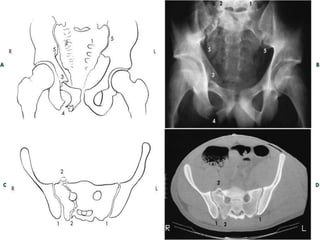

Tile A2 / Young LC II

 6 lines of the pelvis:

 1. Iliopubic (arcuate) line – disruption

indicates ant column injury

 2. Ilioischial line which defines the

posterior column

 3. Teardrop or Roentgenographic U

formed by roof of acetabaulum and

ilioischial spine defines quadrangular

plate – disruption means intraplevic

penetration

 4. Roof of acetabulum

 5. Post rim of acetabulum

 6. Ant rim of acetabulum

 7. Shenton’s line = medial femoral shaft

 obturator foramen: disruption in hip

dislocation or femoral neck #’s